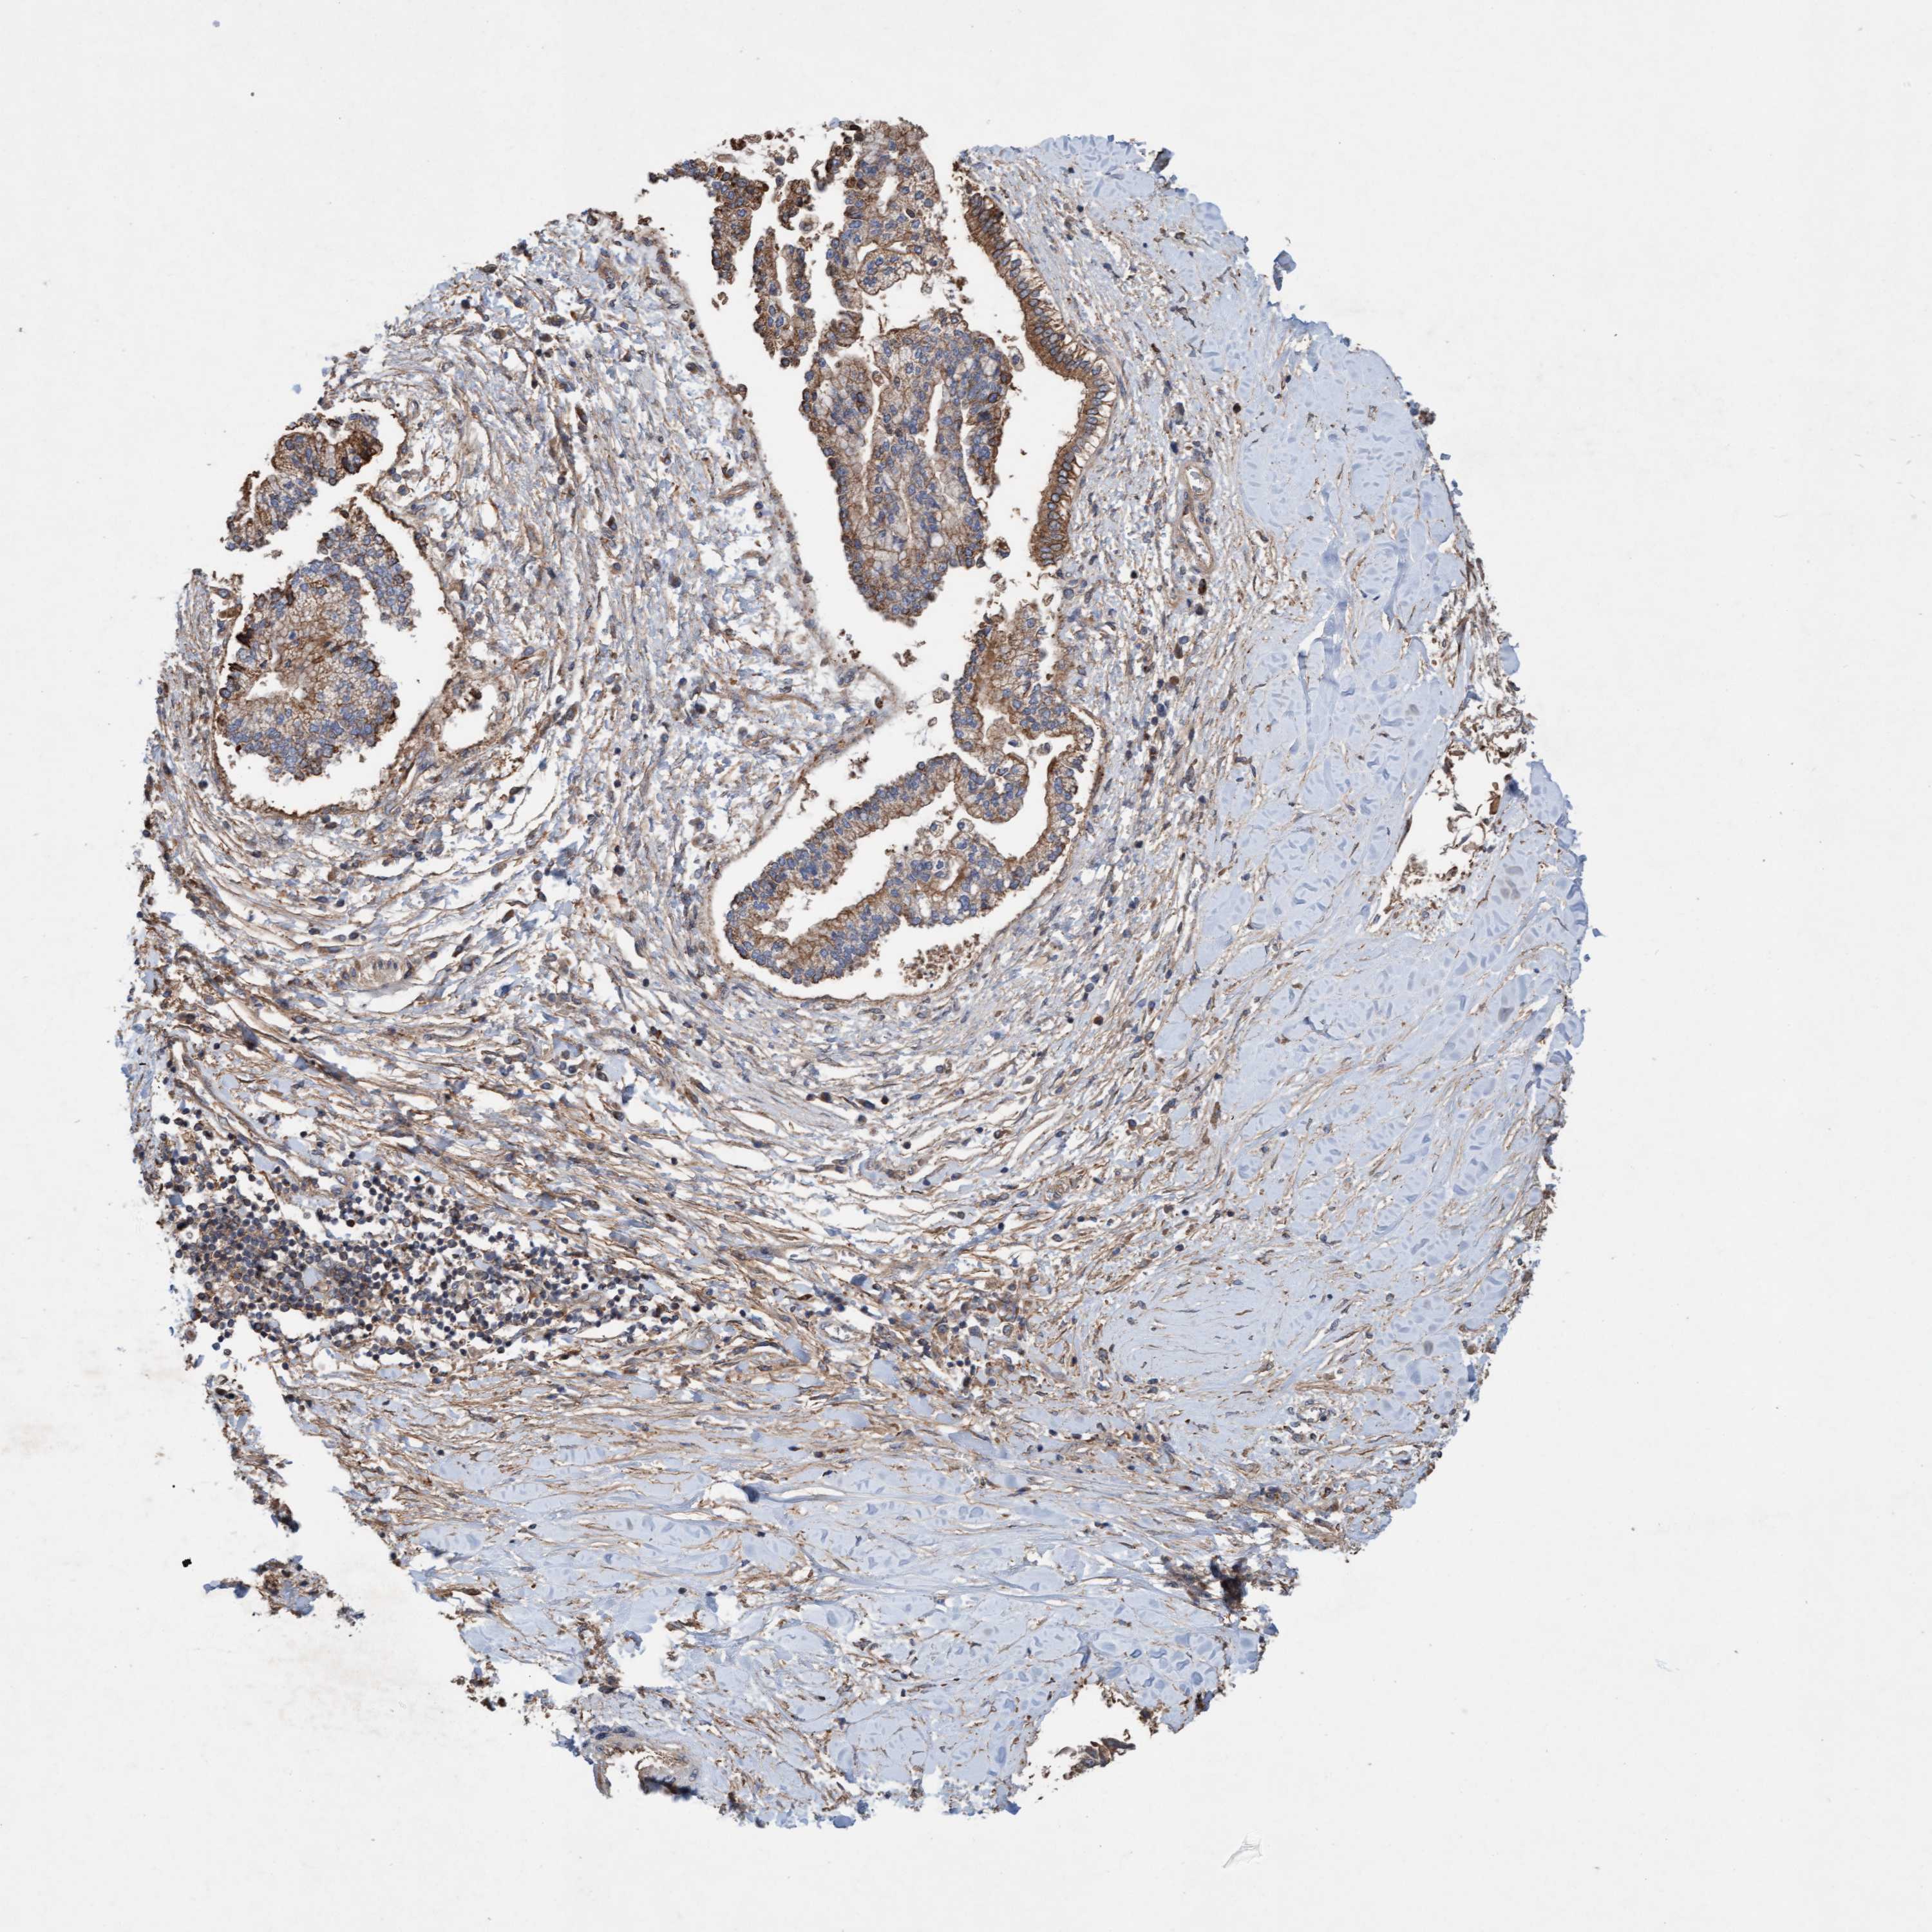

LIVER CANCER - Protein expressioni

A mouse-over function shows sample information and annotation data. Click on an image to view it in a full screen mode. Samples can be filtered based on level of antibody staining by selecting one or several of the following categories: high, medium, low and not detected. The assay and annotation is described here.

Note that samples used for immunohistochemistry by the Human Protein Atlas do not correspond to samples in the TCGA dataset.

Antibody stainingi

Antibody staining in the annotated cell types in the current human tissue is reported as not detected, low, medium, or high, based on conventional immunohistochemistry profiling in selected tissues. This score is based on the combination of the staining intensity and fraction of stained cells.

Each image is clickable and will lead to virtual microscopy that enables deeper exploration of all samples and also displays staining intensity scores, fraction scores and subcellular localization as well as patient and tissue information for each sample.

Antibody HPA021425

Antibody HPA024423

Staining

High

Medium

Low

Not detected

Intensity

Strong

Moderate

Weak

Negative

Quantity

>75%

75%-25%

<25%

None

Location

Nuclear

Cytoplasmic/membranous

Cytoplasmic/membranous,nuclear

Cholangiocarcinoma

Carcinoma, Hepatocellular, NOS